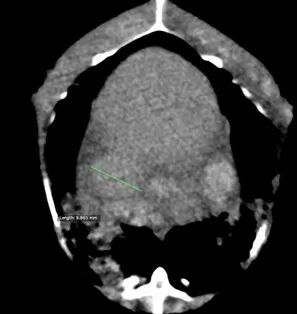

CT平扫:

躯干平扫:双侧肺部存在明显CT值升高区域,右侧较严重。体腔脏器周边存在较多CT值约2HU的均一性物质。肝脏CT值约40HU,肝脏轮廓略钝圆。后腔静脉直径最粗处约10mm。心脏轴面约26*23mm。

肺水肿。体腔积液。充血性心力衰竭。肝脏水肿/脂肪肝。建议结合临床、病史及细胞学和/或组织病理学。